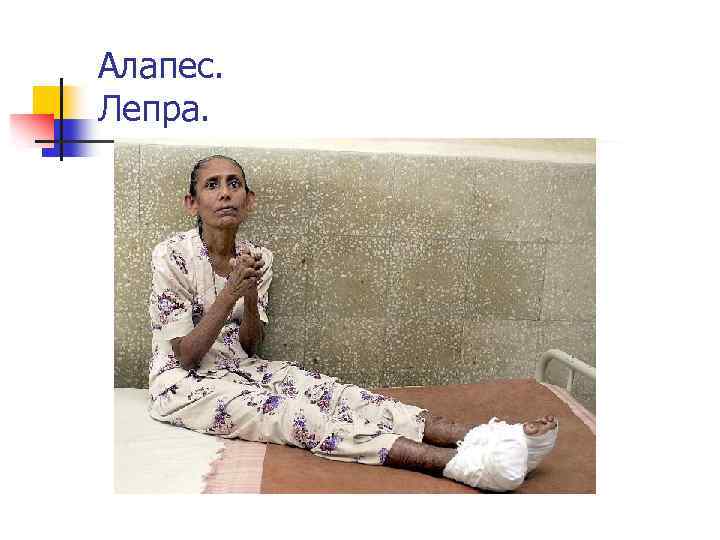

Алапес. Лепра.

Алапес. Жаралар. Лепра. Язвы.

Алапес. Лепра.